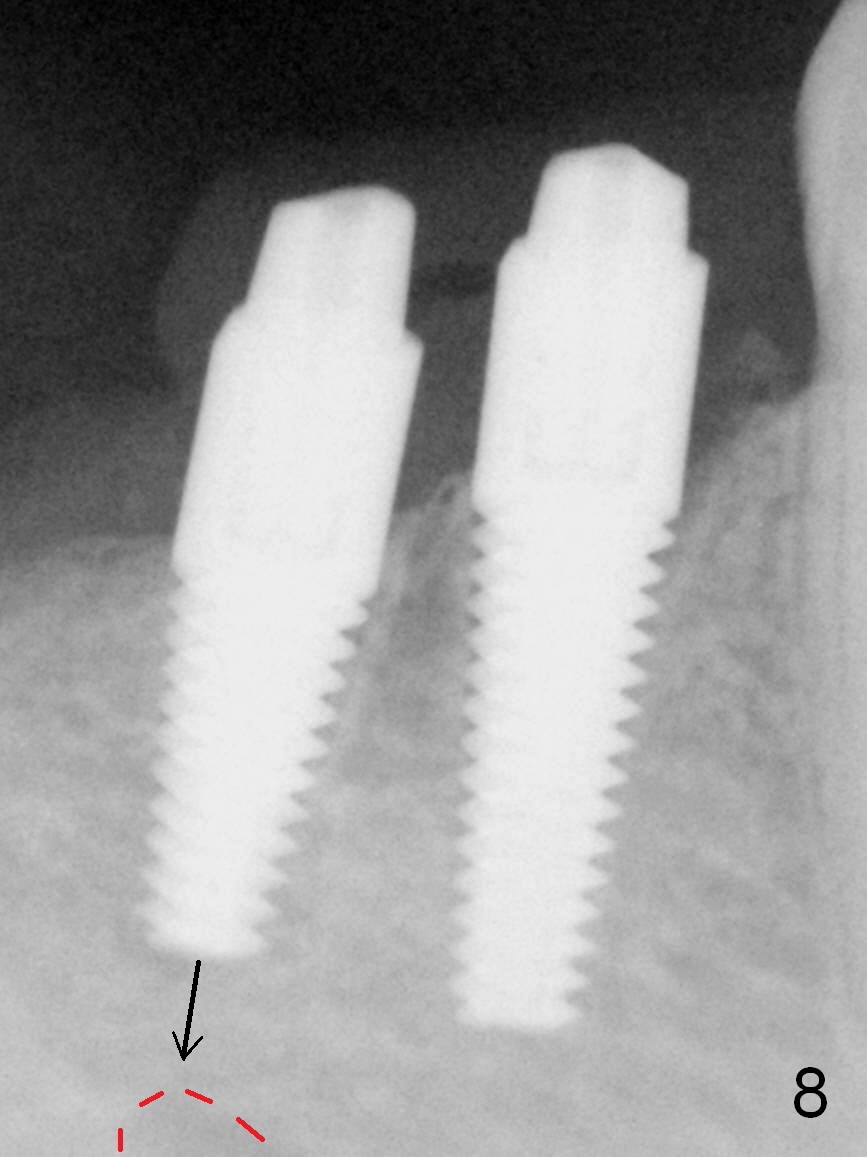

After restoring the implant at the site of #20, the patient returns for #28,29 implant placement (Fig.1,2). Bone level and distance from the Mental Loop (Fig.2 red dashed line) are different. It appears that longer implant can be placed at #28 than that at #29. Parallel pins are placed after initial osteotomy (Fig.3), it appears that the osteotomy at #29 should be moved mesially (arrow). Next PA shows that the position of the osteotomy at #29 is corrected (Fig.4). The position of the implants (4.5x17, 4.5x14 mm) appears ideal (Fig.5). After preparation for an immediate provisional, bone graft is placed in the remaining socket space (Fig.6 *). The splinted provisional is temporarily placed (Fig.7 P). The implant at #29 seems to be buccally placed. After CBCT confirmation, it should be removed for replacement. In addition to moving the osteotomy lingually, there is apparent space (~3 mm) to extend the osteotomy apcially for primary stability (Fig.8 arrow). The apical diameter of the implant is 3 mm.